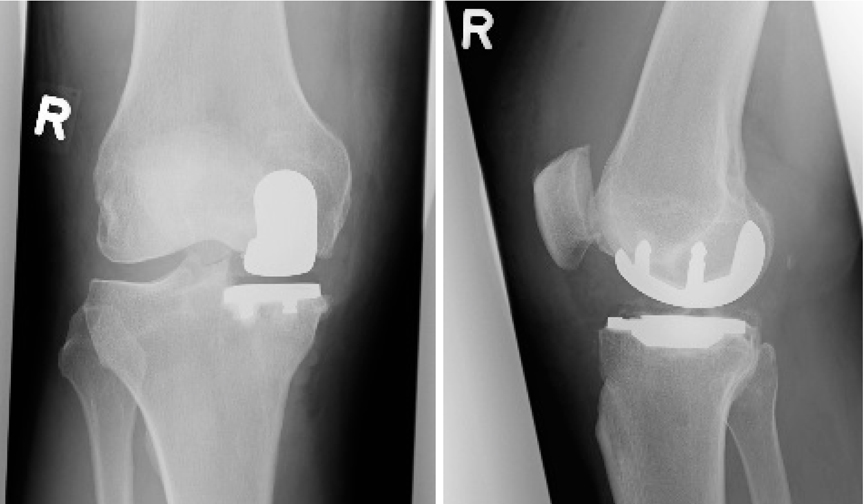

2. „fixed bearing“ Prothesen, bei welchen das Inlay fest mit dem Unterschenkelteil der Prothese verbunden ist. Wir verwenden das Fixed Bearing System der Fa. DePuy, das Sigma partial Knee. (Abb1.)

Abbildung: Fixed Bearing System |